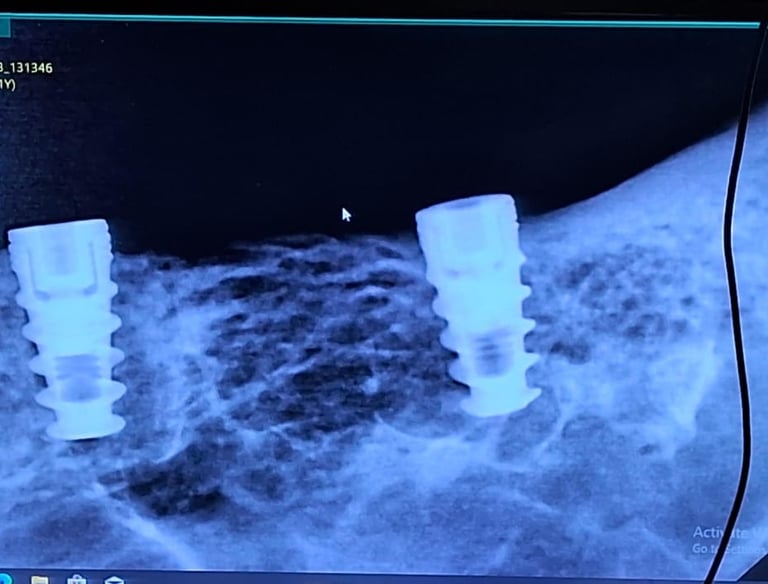

Implant dentistry uses titanium or ceramic posts placed in the jawbone to replace missing teeth. These implants act as artificial roots, supporting natural-looking, fixed or removable teeth.

Implant Dentistry